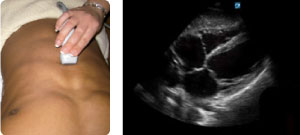

VISTA SUBCOSTAL CARDÍACA

Identifique las estructuras cardíacas y hepáticas, incluyendo VD, VI, RA, LA y el espacio pericárdico. Dirija el transductor hacia el hombro izquierdo del paciente, manteniendo el marcador de orientación hacia la posición a las 3. Busque cualquier líquido libre en el espacio pericárdico. Es la mejor vista para evaluar rápidamente la actividad cardíaca durante la RCP.